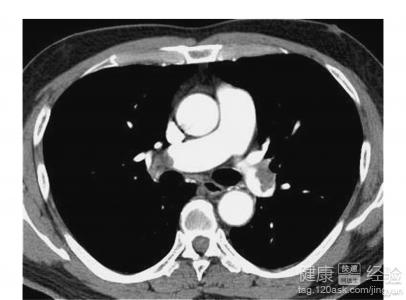

您好,這種情況的話如果覺得有壓迫感的話要考慮是氣胸或者是心髒的原因引起的,如果有心慌的話要考慮是心動過速或者是心動過緩引起的

可以去醫院的心血管內科看一下,必要的話要做一個心電圖以及心髒彩超,有異常的話要做一個心肌酶譜看一下。